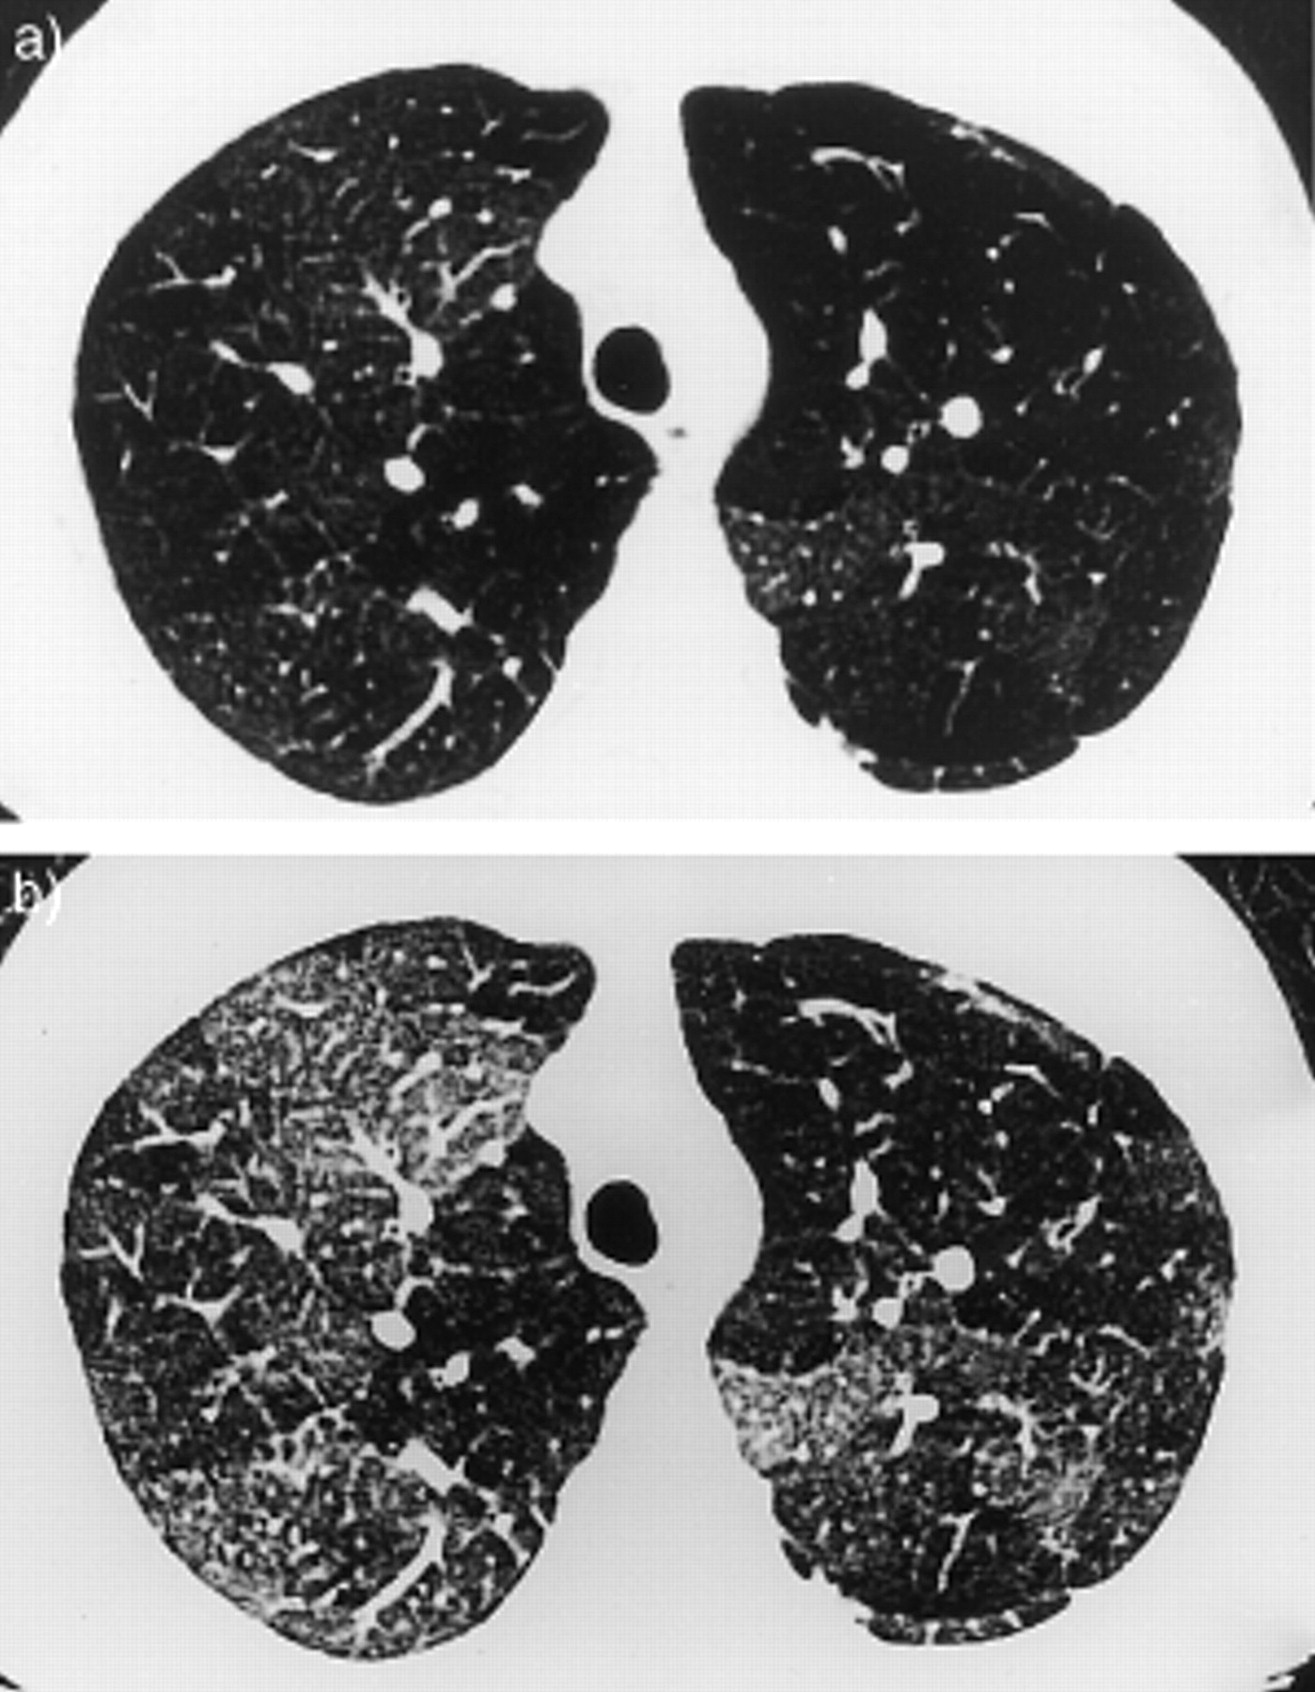

闭塞性细支气管炎( OB):常可致命的罕见疾病,特点为膜性细支气管呈进行性向心性狭窄。OB更常见于女性及类风湿因子检测阳性者。通常表现为急性发作的呼吸困难和咳嗽。起病迅速度和症状严重性往往不符合其他大多数肺病的特点,因此应怀疑此诊断。一般不会出现提示机化性肺炎的表现,包括:发热、体重减轻和不适。体格检查结果包括:吸气性爆裂音和典型的吸气中段吱吱声。HRCT可能会发现支气管壁增厚、小叶中央型肺气肿、有马赛克征的低衰减区域,以及支气管扩张。

RA相关的OB(图片来源见注解4)